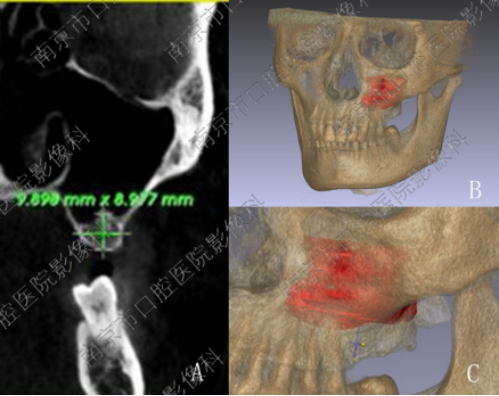

CT检查作为一项三维X线检查技术,可以非常精准地对种植区域进行多方位,多角度的评价,比如对种植区颌骨的体积及质量进行评价,对种植区周围重要解剖结构(上颌窦、鼻底、下颌神经管)进行评价,以及种植区颌骨是否存在病变等。

例如下颌后牙种植时,牙科CT可以精准的测量种植区域颌骨高度,宽度,从而选择合适大小的种植体,避免损伤下牙槽神经。上颌后牙种植的时候,对种植区域颌骨及上颌窦的评价,可以为合理的种植方案的制定提供依据,比如是否需要植骨;上颌窦腔内是否存在炎症,是否需要治疗等。